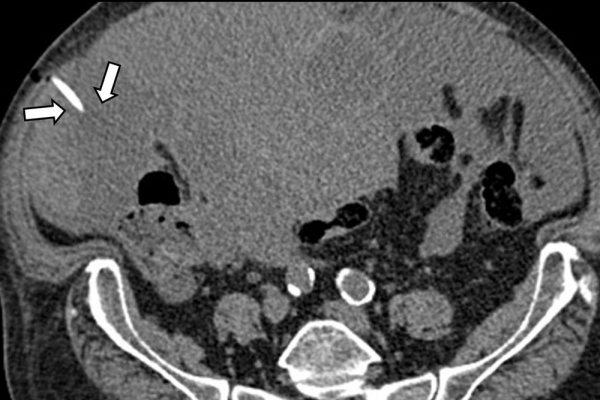

Η παρέμβαση διενεργείται υπό την καθοδήγηση αξονικού τομογράφου ή υπερήχων ή και με συνδυασμό τους. Ο επεμβατικός ακτινολόγος αρχικά αναισθητοποιεί την ανατομική περιοχή ενδιαφέροντος με τη χρήση τοπικής αναισθησίας και παρακεντεί την συλλογή διαδερμικά με λεπτή βελόνη. Στη συνέχεια μέσω ομοαξονικών συστημάτων συρμάτων-καθετήρων-διαστολέωντοποθετείται διαδερμικός καθετήρας τύπου pig-tail εντός της συλλογής, ο οποίος συνδέεται με εξωτερική παροχέτευση.